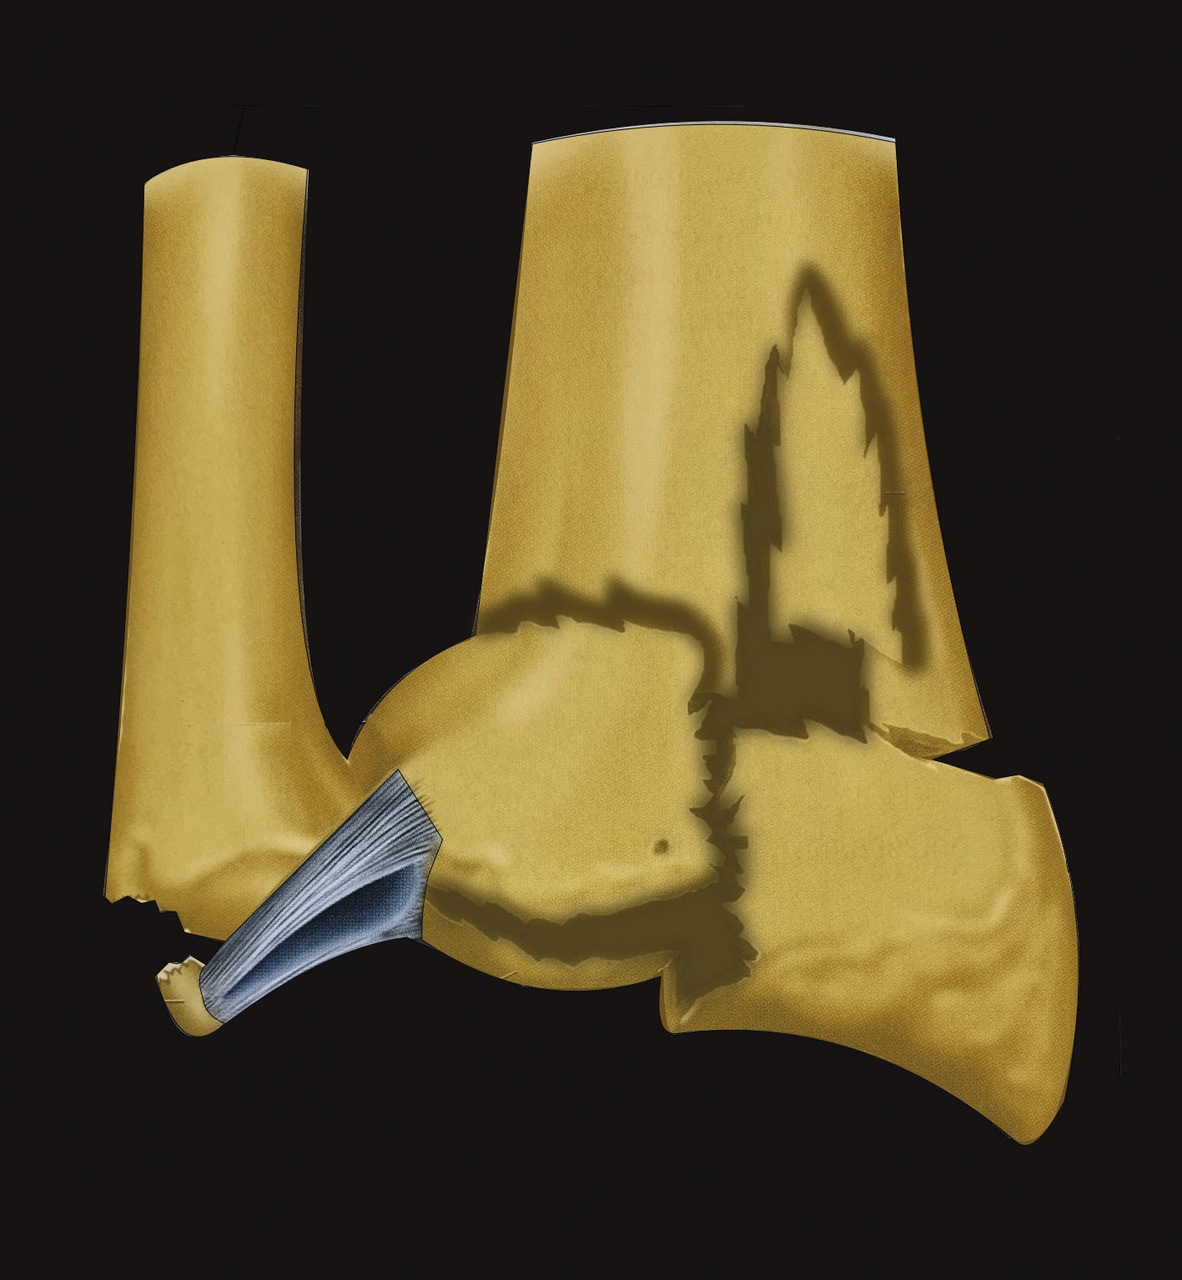

Au niveau métaphysaire le déplacement peut être postérieur ou antérieur (fig. 6). En ce qui concerne le déplacement postérieur, il est important de se souvenir que la surface articulaire regarde vers l’avant. En d’autres termes, dès que cela n’est plus le cas, même si la surface articulaire n’est pas orientée vers l’arrière, il s’agit d’un déplacement postérieur. Classiquement, le déplacement postérieur est lié à un mécanisme dit en compression-­extension, c’est-à-dire une chute sur la main, le poignet étant en extension (fig. 7). Le déplacement est dit antérieur s’il y a une exagération de l’orientation antérieure de l’épiphyse radiale. Ce déplacement est classiquement lié à un mécanisme dit en compression-flexion, c’est-à-dire une chute sur la main, le poignet étant en flexion (fig. 7). La plupart du temps, ce déplacement postérieur ou antérieur s’accompagne également d’un déplacement externe, avec un tassement au niveau de la corticale latérale (fig. 8). Outre le déplacement antérieur, postérieur ou latéral, il est très important d’analyser au niveau du foyer de fracture métaphysaire l’importance de la comminution qui peut être uniquement postérieure, ou antérieure, ou circonférentielle, ce qui conditionne la stabilité de la fracture et oriente vers le type d’ostéosynthèse à réaliser.

L’analyse de l’épiphyse va permettre de déterminer si la fracture est articulaire ou extra-articulaire. Dans la très grande majorité des cas, la fracture est articulaire. Il existe très fréquemment un fragment postéromédial qu’il est important de rechercher car il faudra le stabiliser lors du traitement. Mais la fracture articulaire peut être plus complexe, en T ou en croix (fig. 9). Enfin, il peut exister des enfoncements de fragments ostéochondraux à l’intérieur du spongieux épiphysaire (appelé par les Anglo-Saxons « die punch »). Sur les fragments épiphysaires s’attachent les ligaments radiocarpiens. Ainsi, une traction dans l’axe permet, par le biais de ses ligaments (effet de ligamentotaxis), de réduire au moins partiellement la fracture. En revanche, les fragments ostéochondraux qui sont enfoncés dans le spongieux n’ont pas d’attaches ligamentaires et ne se réduisent pas par les manœuvres de traction. Il peut arriver que les fractures soient uniquement épiphysaires. C’est le cas des fractures dites marginale antérieure, marginale postérieure et cunéenne externe. Cette dernière est importante à connaître et à dépister car elle s’accompagne relativement fréquemment de lésion ligamentaire intracarpienne, notamment scapholunaire.

Enfin, il est important d’analyser le versant ulnaire pour savoir si la fracture de l’extrémité inférieure du radius est isolée ou bien associée à une fracture de l’extrémité distale de l’ulna ou encore à une fracture de la styloïde ulnaire. Cette fracture est l’équivalent d’un arrachement du ligament triangulaire du carpe et peut être source d’instabilité radio-ulnaire distale (fig. 10). Il faut également analyser le rapport entre l’épiphyse radiale et l’épiphyse ulnaire, à la recherche d’une inversion de l’index radio-ulnaire témoin d’une ascension de l’épiphyse radiale.